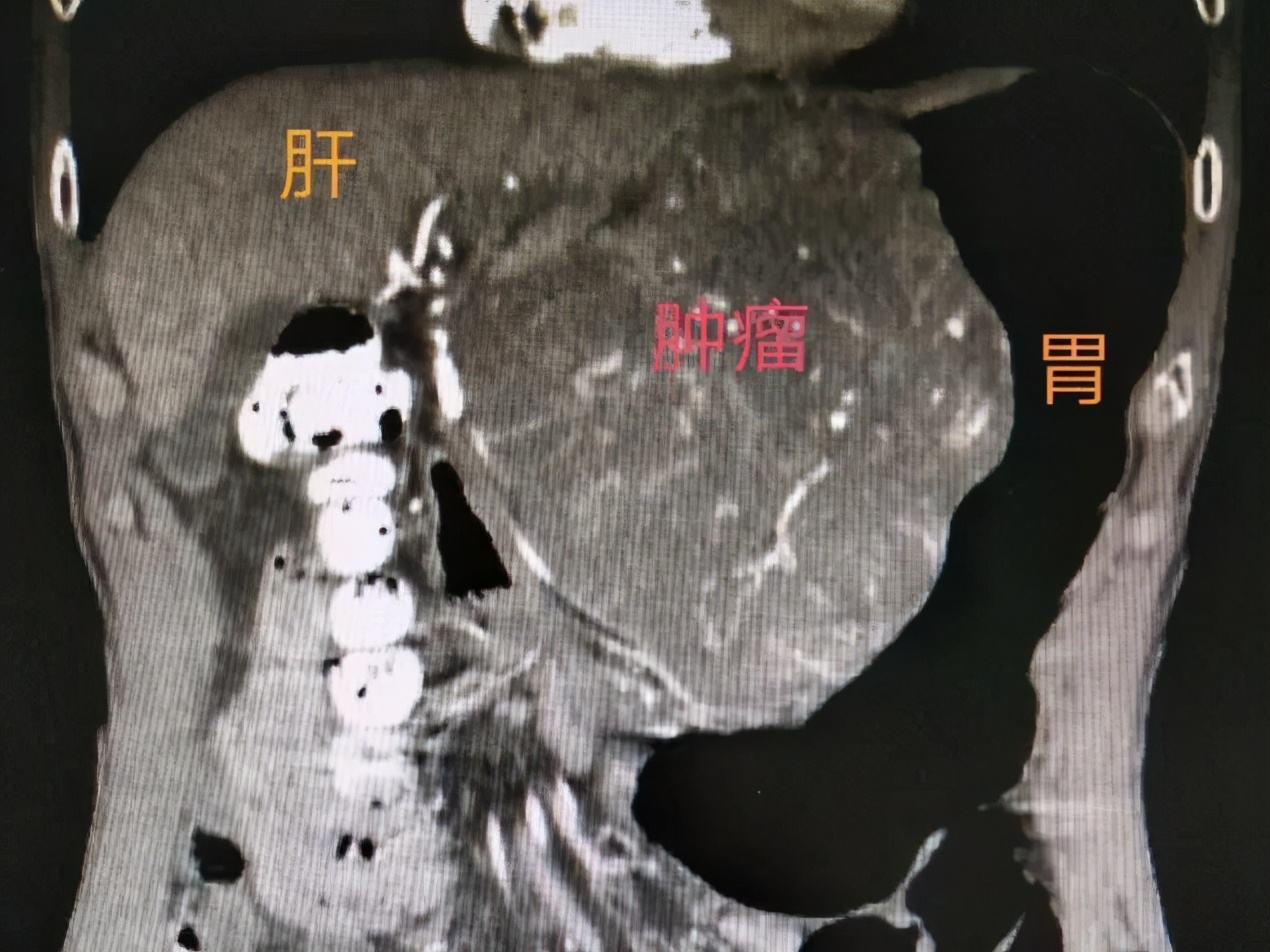

2020-2-2转化治疗前CT示肿瘤巨大

今年1月,李先生出现上腹隐痛不适,在当地县医院发现左上腹区占位性病变后,经人介绍来到桂林医学院第二附属医院胃肠外科住院治疗。经检查发现一个紧贴肝和腹膜后大血管、大小约152mm×128mm×78cm的肿块。胃肠外科副主任陈伟教授组织MDT讨论,认为胃巨大间质瘤可能性大,初步判断为原发不可切除型,此时如果勉强手术,可能术中大出血且行全胃甚至联合脏器切除可能性高,损伤代价太大,完整切除肿瘤的可能性也很小,如肿瘤破裂或残留则极易复发,治疗效果不佳。

2月5日,超声科为李先生行超声引导下腹腔肿块穿刺活检,病理检查确诊为(胃)间质瘤,李先生开始口服靶向药物伊马替尼进行转化治疗。至11月15日复查,肿瘤已缩小至68mm×56mm×55cm。